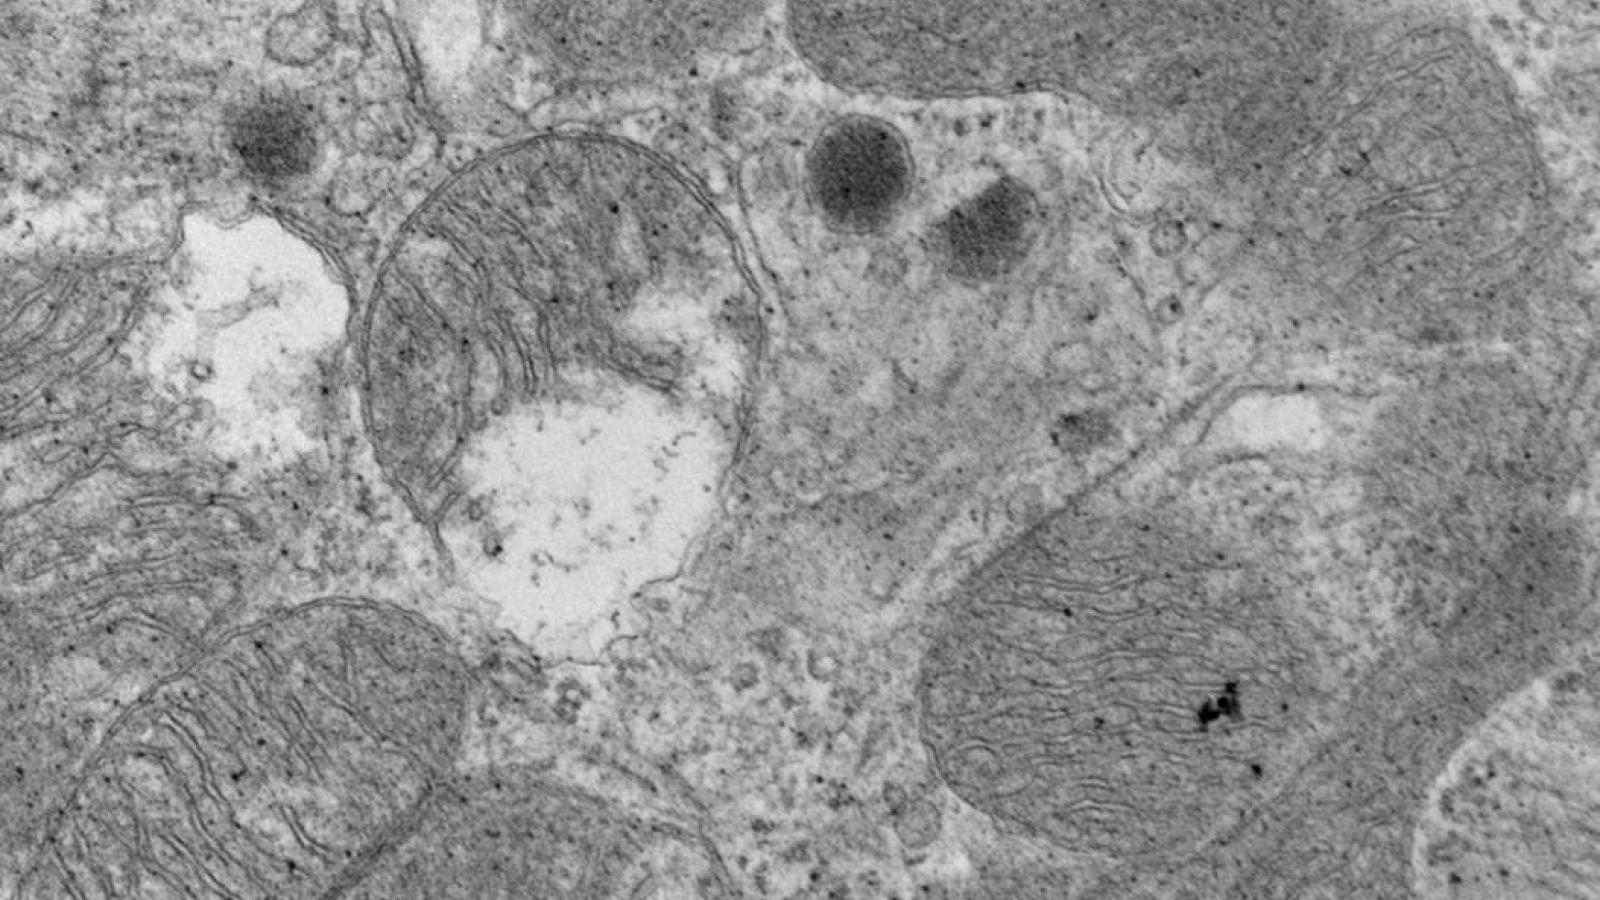

The Marx Lab studies the regulation of ion channels by macromolecular complexes. We have demonstrated that specific sequences within the ion channel (leucine zippers) recruit regulatory proteins, which modulate the ion channel function in normal and pathologic conditions. The laboratory is now focused on understanding the molecular components and functional implications of macromolecular complex formation of the large conductance calcium-activated potassium channel (BKCa, maxi-K) and the L-type voltage gated calcium channel. The laboratory utilizes both molecular biologic and electrophysiologic (planar lipid bilayer, patch clamp) techniques to elucidate these fundamental processes and emphasizes the links between these fundamental molecular processes and systems function. To date our work has had significant impact in understanding the triggers of fatal cardiac arrhythmias and mechanical dysfunction in heart failure. Present experiments are very likely to impact our understanding of control of peripheral blood pressure by the sympathetic nervous system.

- Cardiac: studying the regulation of ion channels in normal and pathological conditions in the heart. Altered cardiac ion channel function is associated with heart failure and arrhythmias.